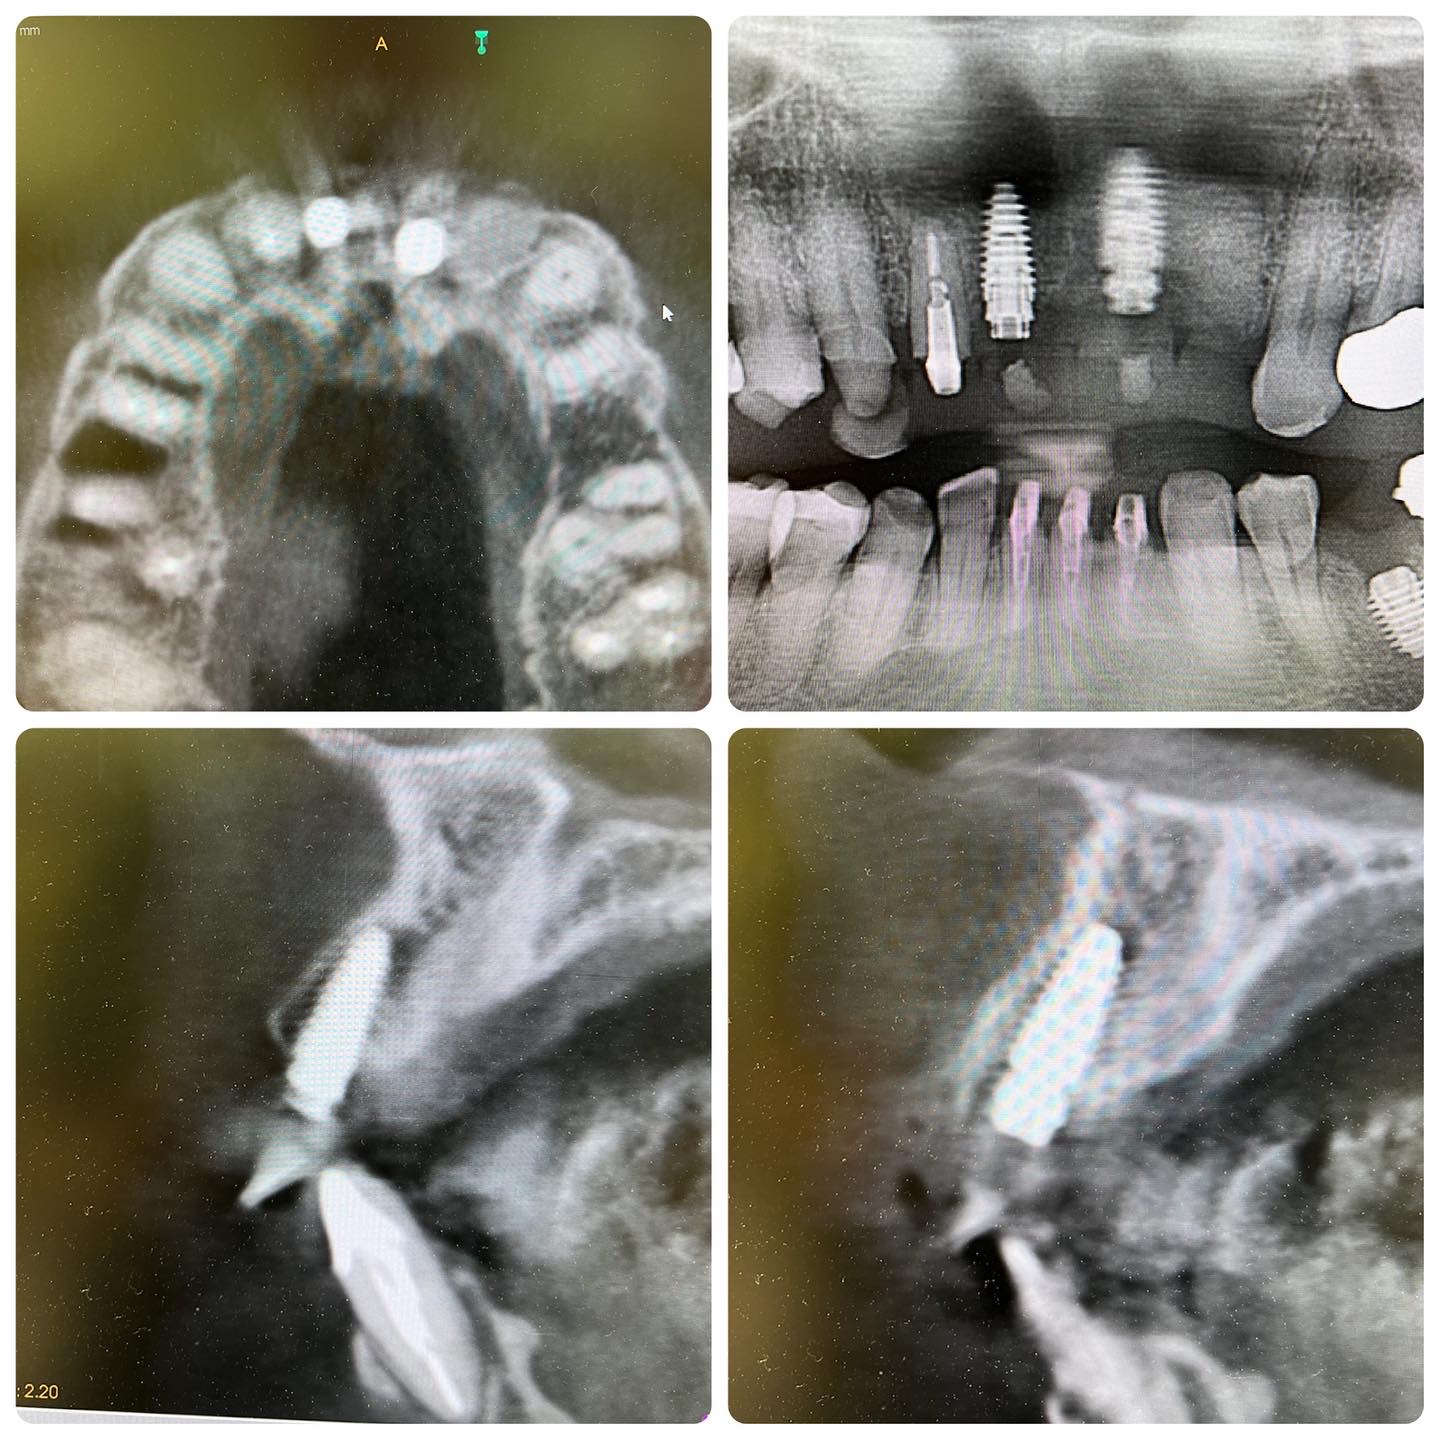

前歯部歯根破折

バイトアップ→インプラント埋入スペース確保→1,1osseodenfication burにて#抜歯即時埋入+#DualZoneTechnique→22#Bio-0ssにて#ARP+#machaskitchenOvate延長Pontic→#上唇小帯切除術

| 治療費(税込) | インプラント2本埋入とridge preservationとオベイトポンティックとテンポラリーアバットメント

66万円 |

| リスク・副作用 | 術者の優れた知識と技術が必要とされる |